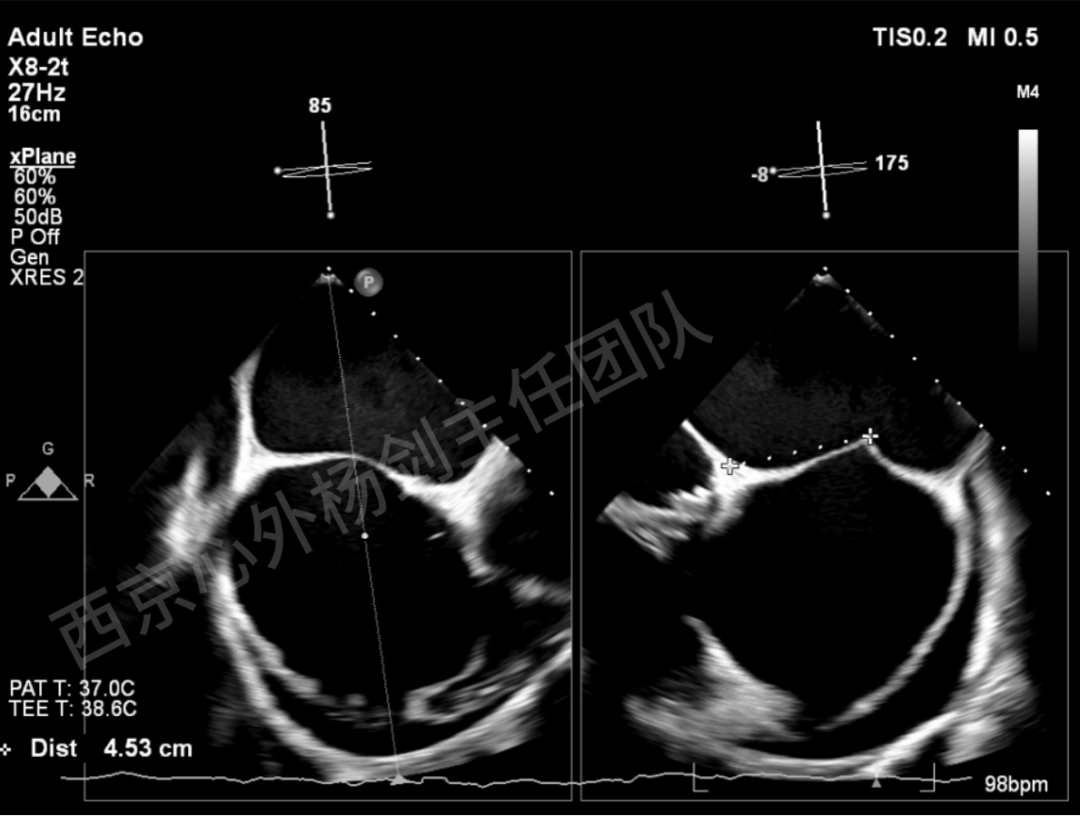

TAVR术后,全心增大,二尖瓣反流重度,三尖瓣反流重度。中量心包积液。左室严重增大,标准图像调整困难。主动脉瓣位带支架人工瓣膜瓣叶启闭正常,主动脉瓣位人工瓣上血流速度Vmax 148cm/s,PGmax 9mmHg,Vmean 86cm/s,PGmean 2mmHg, VTI 34.7cm,瓣周反流(轻)。估测肺动脉收缩压约49mmHg;左室收缩功能明显减低。LVEF:23%,EDV:364ml,ESV:221ml。

彩色血流示:二尖瓣反流缩流颈彩宽6.6mm,面积17cm²,容积30ml;二尖瓣瓣口面积6.6cm²,瓣环内径:左右径34mm,前后径34mm。2区瓣叶长度:前叶36mm,后叶20mm,叶环比1.6. 三尖反流面积17.2cm²,容积33ml,Vmax 291cm/s,PGmax 34mmHg。

TEER术前超声评估

二尖瓣后叶栓系严重,前叶相对错位,反流束沿2区分布广泛,2偏3区处存在反流。

反流宽度至少23mm,因影像调整困难,考虑实际反流更宽。